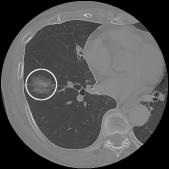

Automatic extraction of laesio part on lung CT images

We develop a Computer Aided Diagnosis(CAD) system which extracts laesio parts automatically.